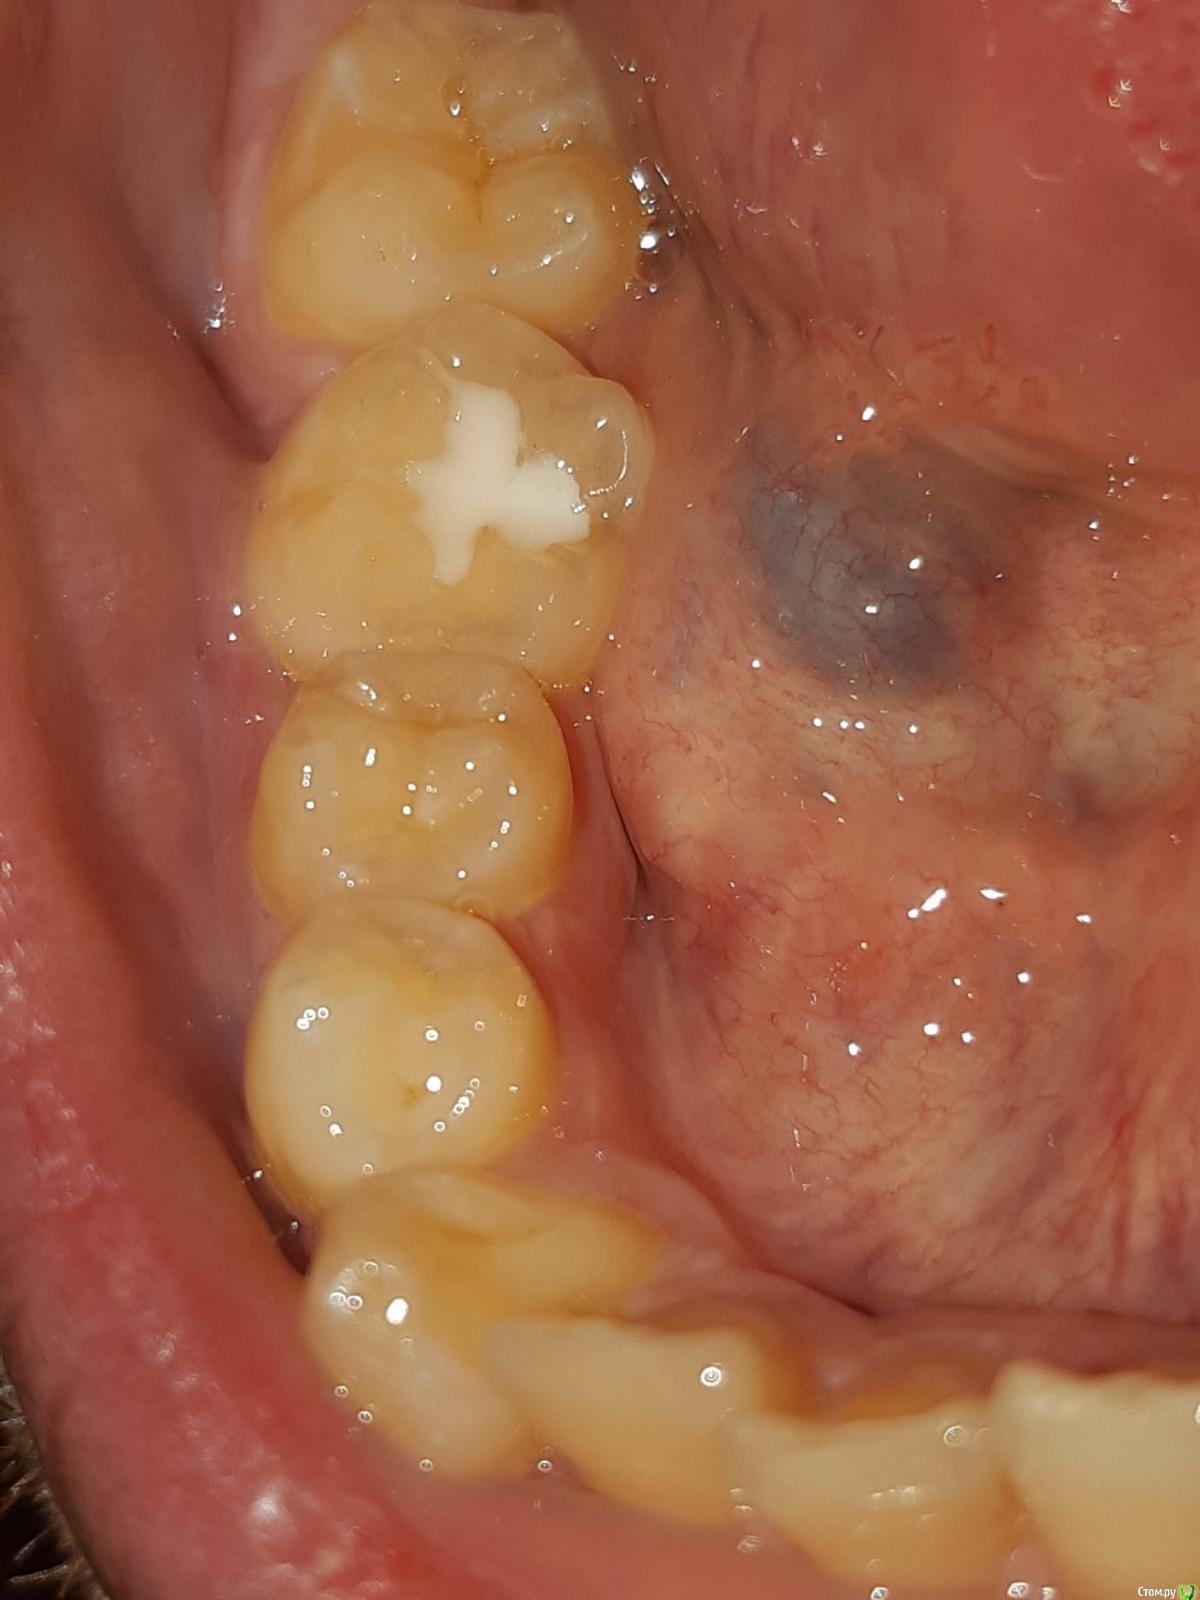

В итоге он старую пломбу удалял мне полчаса под микроскопом и не знаю почему, но было х10 больнее и пломбу он цементную поставил х10 больше и как будто пересверлил мне всю коронку. В зеркало когда пришел домой увидел- был шок. К сожалению фотографию предыдущей пломбы я не сделал ! Что очень обидно.

Фотографии с последнего вида пломбы и с КТ прилагаю.

JjNWg3t_d6Y.jpgyRfi2zSBvsg.jpg

post-61616-0-62659300-1603773681_thumb.jpg